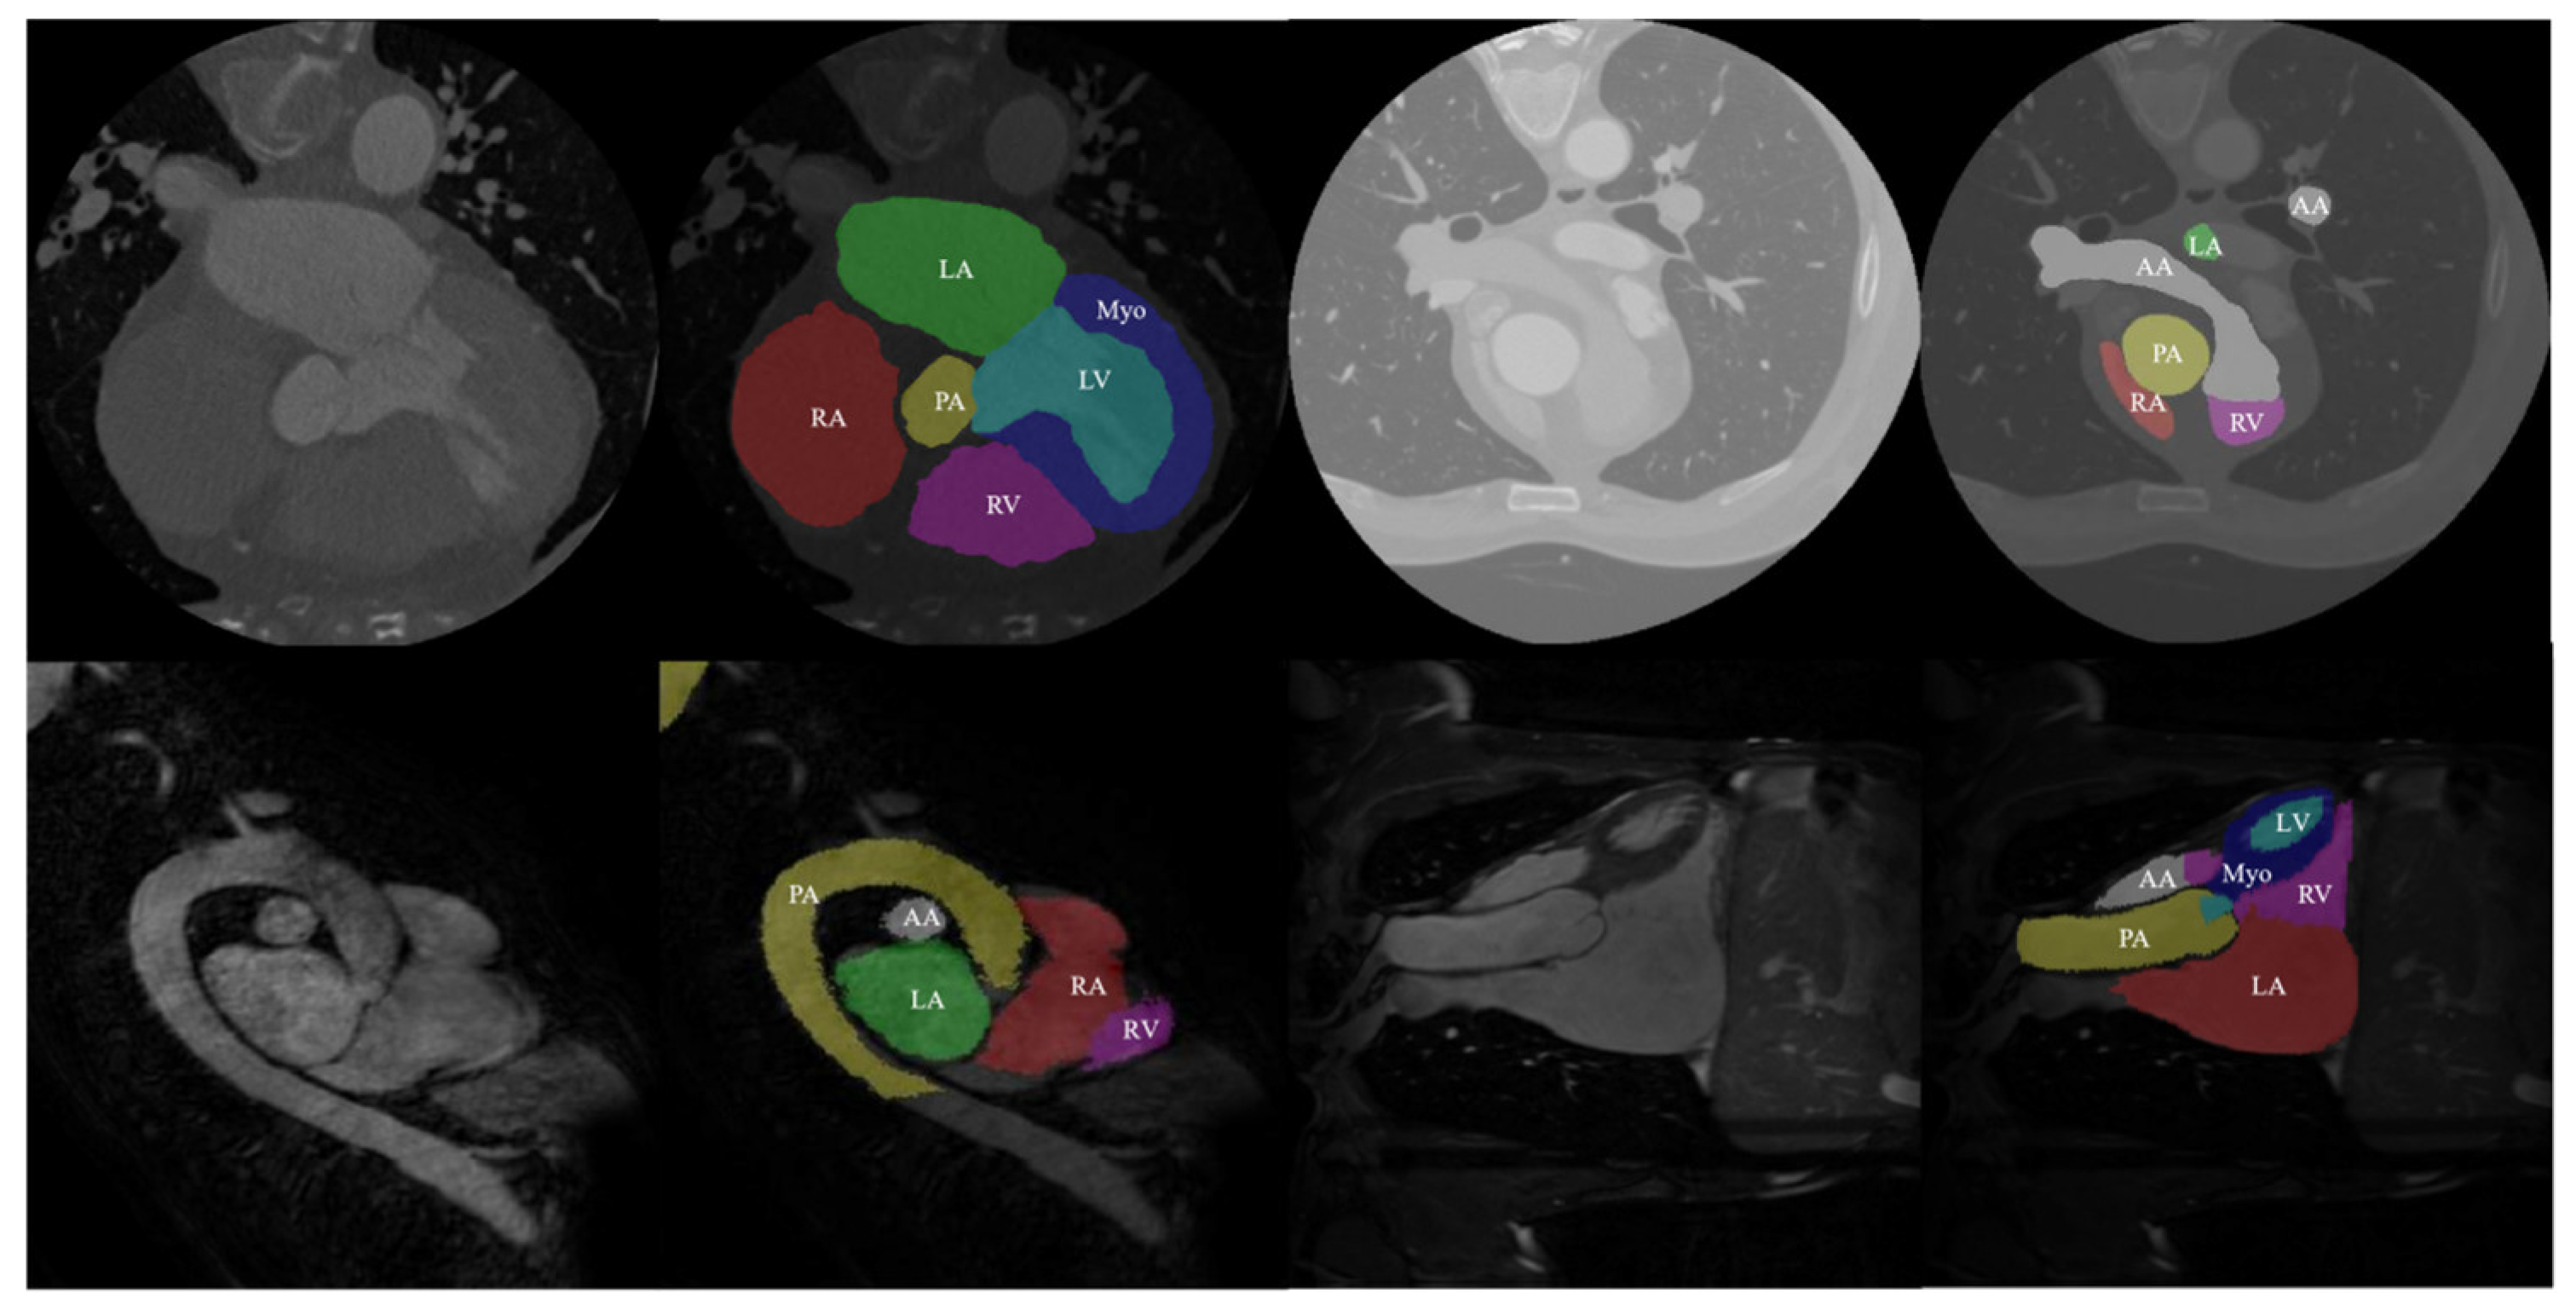

The data used in this study came from the MM-WHS Challenge 2017 open-source dataset. This dataset includes 20 labeled cardiac CT image training sets, 20 labeled cardiac MRI image training sets, 40 unlabeled CT images, and 40 unlabeled MRI images. All data in this dataset are three-dimensional (3D) medical images with real value labels for the heart. Specifically, these labels include seven cardiac substructures: ascending aorta (AA), pulmonary artery (PA), left atrium (LA), left ventricle (LV), left ventricular myocardium (Myo), right atrium (RA), and right ventricle (RV) (as shown in Figure 6). The first row of Figure 6 displays the CT images and their corresponding real labels, while the second row displays the MRI images and their corresponding real labels.

Processing this dataset poses multiple challenges. Firstly, the complexity and diversity of 3D medical image data increase the difficulty of analysis and processing. Different imaging modalities (CT and MRI) have varying contrasts and resolutions, requiring the model to adapt to these variations. Additionally, the boundaries between cardiac substructures are often blurred, with complex shapes and overlapping structures further complicating the segmentation task.

Figure 6. Data and true labels in the dataset.